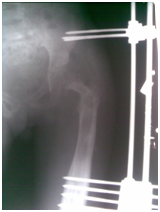

Figure 1 Initial radio graph- Femoral head dislocated supra-laterally, Shaper cook deformity of left femoral cortices are sclerosed, a large hyper dense area in the medullary cavity sequestrum. Pelvis tilted on the right.

Figure 2 Across hip Naseer Awais External Fixator applied for control distraction of proximally migrated femoral head, 2mm per day.

Figure 3&4 Showing distraction started process is going on 2mm per day, to avoid Neuro-vascular injury.

Figure 5 showing Radiograph 3 weeks after distraction is on progress by applying NA Ex Fix.